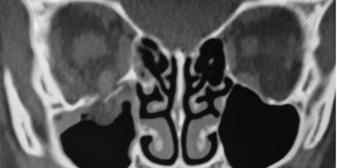

Una fractura deprimida del suelo orbitario derecho (fractura por estallido) se acompaña de una hernia de grasa orbitaria en la cara superior del seno maxilar y atrapamiento del músculo recto inferior (signo de la lagrima).

ETMOIDES UNGUIS MAXILAR PALATINO CIGOMÁTICO ESFENOIDES

Figura 71. Los 7 huesos que forman parte de la órbita, recordar que la lámina papirácea forma parte del hueso etmoides

Figura 72. Fractura del piso o suelo orbitario Figura 73. Fractura del piso o suelo orbitario Prueba de motilidad ocular. La mirada hacia arriba del ojo derecho está restringida como resultado del atrapamiento del recto inferior.